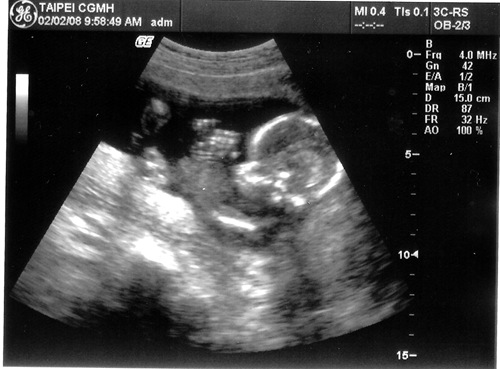

[產檢] 17週 寶寶頭大不是我的錯~~ ><

感覺有點擠~~

項  目 數 據 結 果 備 註

地點 02/02台北長庚 例行產檢

週數 17週

身長 15cm 體重約200g  ;  OK

心跳 150下/分鐘 OK

其他檢查 唐氏症抽血篩檢 預約高層次超音波

這星期主要還是看看超音波

量量寶寶的身長和估算體重有沒有在正常範圍

老婆邊照邊說寶寶頭很大..

沒想到醫生還跟著老婆瞎起鬨

說寶寶頭大像爸爸喔!!!   (明明寶寶頭的比例本來就比身體大得多...)   生氣...

這次照的超音波照也很清楚喔!!  真讚!!

寶寶還擺出鹹蛋超人的手交叉的動作..  五根手指己經看得清清楚楚了